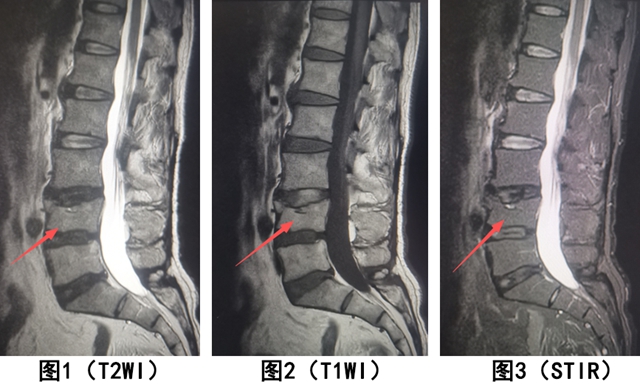

【案例2】患者男,腰背部间断性病痛,曾有腰部受伤史。作腰椎MRI检查,如下图。

腰椎 MRI 显示:L4 椎体呈楔形变(陈旧骨折的形态改变),但所有成像序列的信号都和正常椎体一致(无水肿,骨痂已愈合)。

结论:L4 椎体陈旧性压缩骨折。

关键:形态异常 + 信号正常(提示愈合已久,无水肿)。